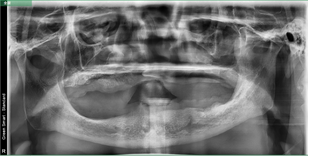

術(shù)前片/術(shù)后片

患者,男性,60歲。

主訴:上頜無牙頜,下頜多牙體缺失,余留牙體松動(dòng)不適,進(jìn)食效率低下(困難)明顯,要求治療。

治療方案:完善相關(guān)化驗(yàn)檢查,定制放射導(dǎo)板和種植導(dǎo)板,松動(dòng)牙拔除,并行數(shù)字化全口種植桿卡修復(fù)治療。

術(shù)前片/放射導(dǎo)板定制曲斷片